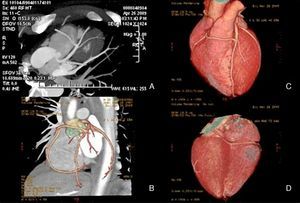

Imagens de TC cardíaca-64 cortes. As imagens A (imagem reconstruida tipo MIP) e B (imagem reconstruída tipo «volume rendering») evidenciam a origem da CD anómala no segmento médio da DA; Note-se, nas imagem C (imagem reconstruída tipo «volume rendering»), o trajeto da CD anterior aos grandes vasos e na imagem D (imagem reconstruída tipo «volume rendering»), a escassez de suprimento arterial epicárdico posterior e inferior por ausência de artérias póstero-lateral e descendente posterior.

Foi internado na unidade de cuidados intensivos coronários com diagnóstico de síndrome coronária aguda sem elevação do segmento ST e foi submetido a cateterismo urgente. A coronariografia excluiu doença aterosclerótica luminal, mas mostrou a presença de uma ACC. O doente apresentava um ostium coronário único em posição do Seio de Valsalva esquerdo, que originava o tronco comum. Este vaso apresentava um trajeto normal bifurcando-se numa artéria descendente anterior (DA) e numa artéria circunflexa com as distribuições anatómicas habituais. Por sua vez, a artéria coronária direita (CD) originava-se de forma anómala no segmento médio da DA e dirigia-se depois para a direita para vascularizar o seu território habitual. Para melhor definir as correlações anatómicas da coronária direita, realizou-se um AngioTC, que excluiu trajetos malignos deste vaso entre a aorta e a artéria pulmonar e documentou uma aparente escassez de suprimento arterial epicárdico nas paredes posterior e inferior, por ausência das artérias descendente posterior e póstero-lateral. O score de cálcio era 0.